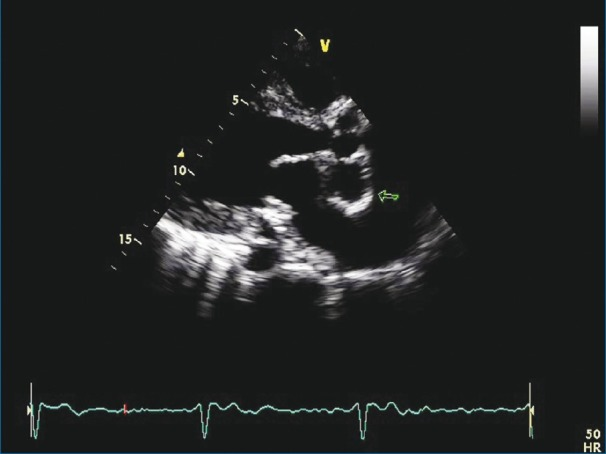

Mitral Aortic Intervalvular Fibrosa MAIF

Fibrous region of the heart that connects the anterior mitral leaflet to the posterior aortic root and communicates with the left ventricular outflow tract

MAIF Pseudoaneurysm